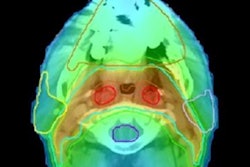

Rapid, accurate, automated segmentation algorithms are needed to handle large volumes of images that adaptive radiotherapy requires. Echo sequences optimized to better visualize the prostate can improve segmentation accuracy. Image credit: Maria Schmidt, Royal Marsden Hospital/Institute of Cancer Research. Reprinted from Int. J. Radiat. Oncol. Biol. Phys. doi: 10.1016/j.ijrobp.2017.10.020 © 2017, with permission from Elsevier.Using adaptive MRI-guided treatments, prostate patients could benefit from more extreme hypofractionation than is currently achievable with external beams, including, potentially, single fraction treatments. Reduced fractions cut the numbers of clinic visits for patients, increase patient throughput, and could improve clinical outcomes.